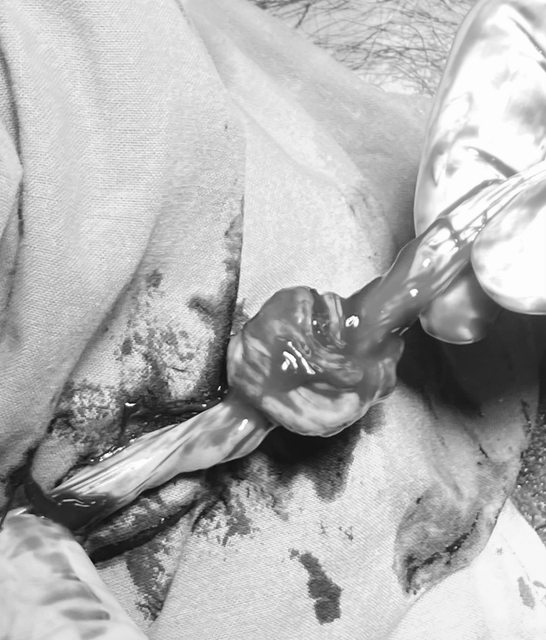

這就是傳說中的臍帶死結(已黑白處理,但還是慎入)

https://i.imgur.com/YQIrGdw.jpg